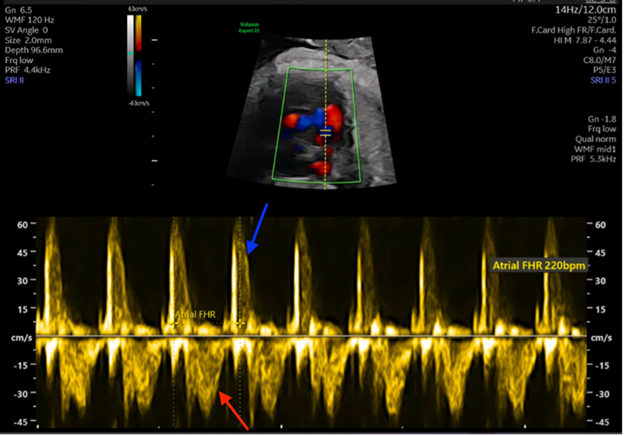

Figure 4: Simultaneous PW Doppler Interrogation of LV Inflow and Outflow Demonstrate a 1:1 A-V Relationship

Figure 4: Simultaneous PW Doppler Interrogation of LV Inflow and Outflow Demonstrate a 1:1 A-V Relationship. Courtesy of Ramachandra R, Ho DY.

Red arrow: inflow wave from atrial contraction. Blue arrow: outflow wave from ventricular contraction.

A-V = atrial-ventricular; LV = left ventricular; PW = pulsed-wave.

Figures 1 and 2 demonstrate a 1:1 atrial-ventricular (A-V) relationship, with one ventricular contraction for every atrial contraction and a short ventriculoatrial (VA) interval. Labeled versions of the images are shown in Figures 3 and 4. This fetus most likely had a re-entrant supraventricular tachycardia (SVT), which typically has a rate between 220 and 300 bpm and a 1:1 A-V relationship with a short VA interval (Figure 3). In contrast, ectopic atrial tachycardia, permanent junctional reciprocating tachycardia, and sinus tachycardia have a 1:1 A-V relationship with a long VA interval. In the setting of atrial flutter (AFL), atrial rates are typically 350-500 bpm with consistent or varying rates of atrioventricular (AV) block (2:1, 3:1, or 4:1). The resultant ventricular HRs are a proportional fraction of the atrial rate.